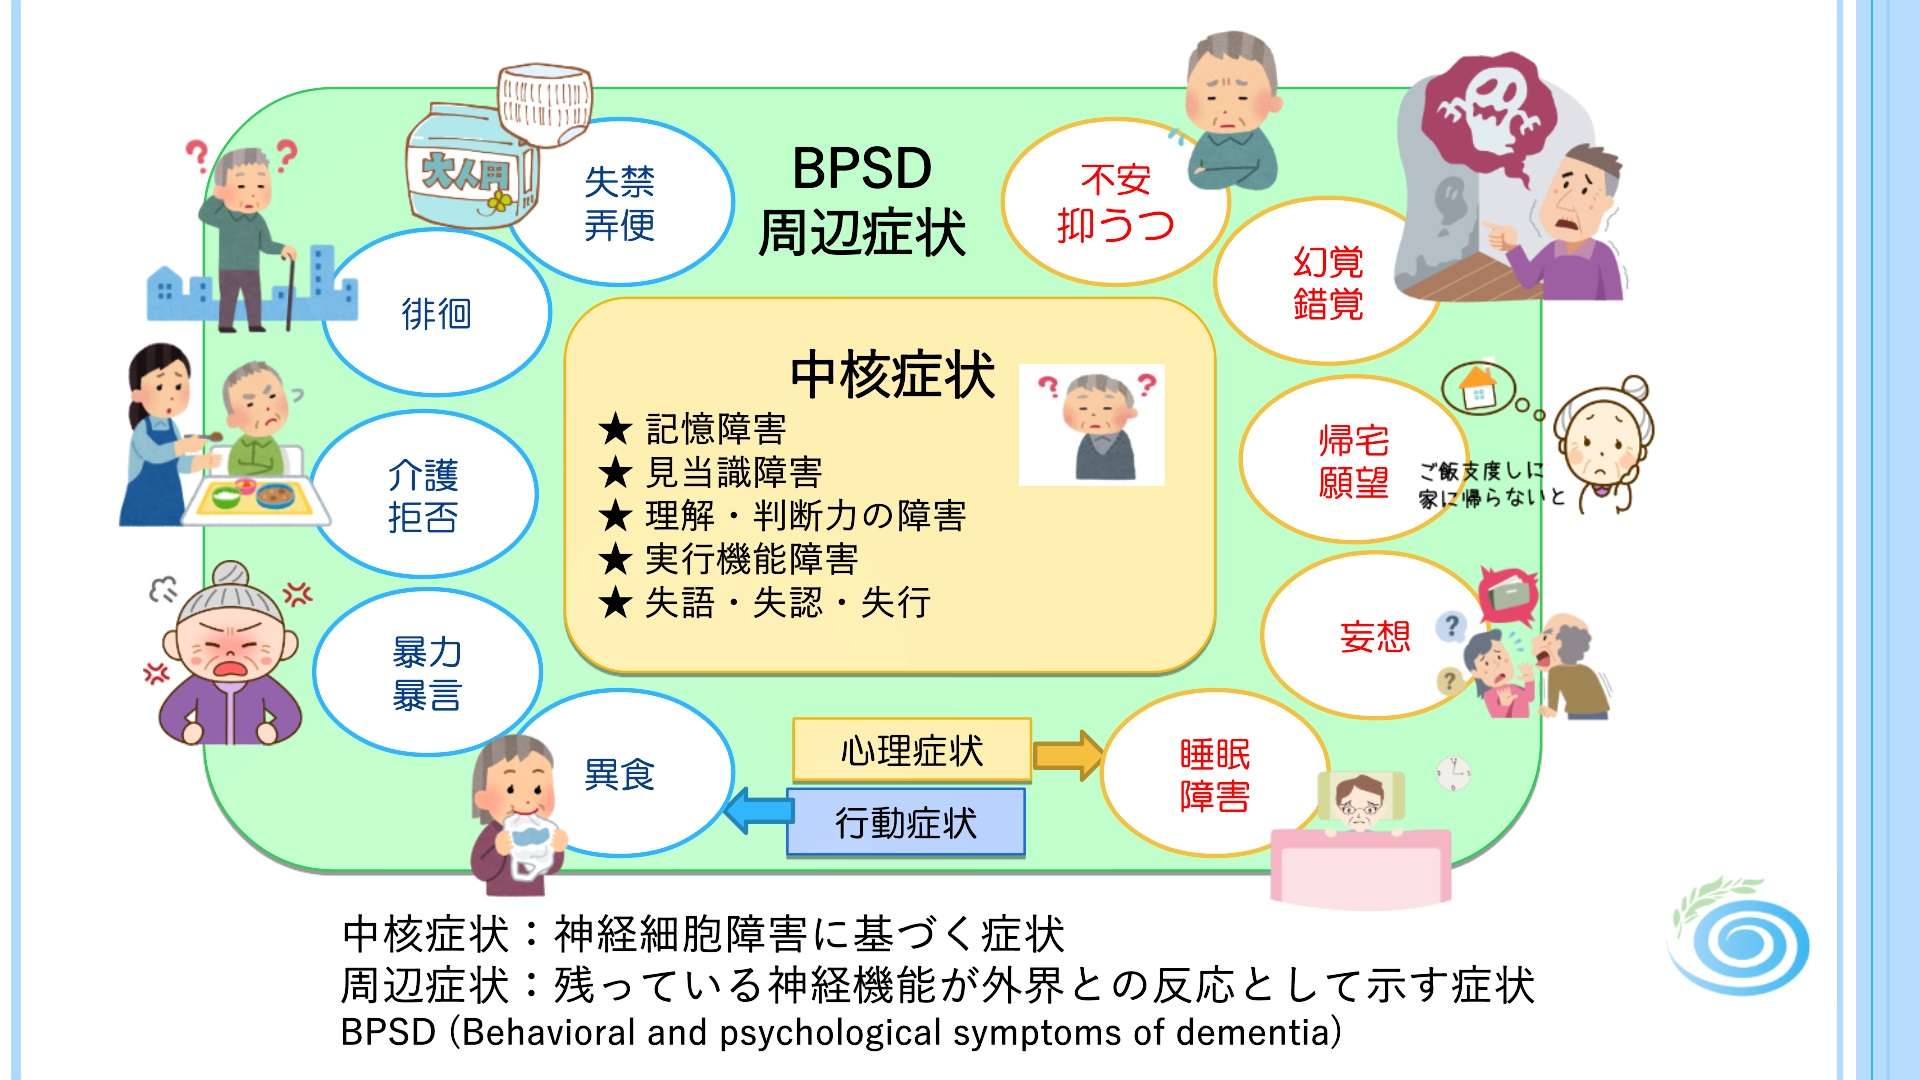

認知症の症状には、

大きく分けて 「中核症状」 と 「周辺症状(BPSD)」 の2つがあります。

この2つはしばしば混同されますが、

背景となるメカニズムが異なるため、区別して理解することが非常に重要です。

■ 中核症状:脳の神経細胞の障害によって起こる“本質的な症状”

中核症状は、認知症の原因となっている脳の病変(神経細胞の減少やネットワーク障害)によって直接生じる症状です。

どのタイプの認知症でも共通してみられる「核となる症状」で、以下のような能力の低下が起こります。

● 記憶障害

新しい出来事を覚えられない、同じ質問を繰り返す、約束を忘れるなど。

● 見当識障害

今日が何日なのか、今いる場所はどこか、季節や時間帯の理解が難しくなる。

● 理解力・判断力の低下

説明を理解しづらい、状況に合った判断が難しい、段取りを組む力が低下する。

● 実行機能障害

家事や買い物、料理、金銭管理など、複数の行動を組み立てることが難しくなる。

● 失語・失行・失認

言葉が出てこない、手順が分からない、物の用途が分からない、見えていても認識できないなど。

これらは“脳そのものの変化”によって生じるため、

周りの関わり方や環境の変化だけで大きく改善するものではありません。

■ 周辺症状(BPSD):環境・心理・身体の要因が関わる“反応としての症状”

周辺症状(BPSD:Behavioral and Psychological Symptoms of Dementia)は、

認知症のある方の日常の中でみられる心理・行動の変化で、

神経細胞そのものの障害だけでは説明しきれない症状です。

国際老年精神医学会は、BPSDを次のように定義しています。

「知覚・思考・気分・行動の異常として現れる、認知症に伴う多様な症状」

つまり、周辺症状(BPSD)とは、

認知症による記憶障害などを背景に、

環境や関わり方、不安や混乱が引き金となって現れる症状ということです。

そのため、同じ認知症であっても、

生活環境や家族との関係性によって現れ方が大きく異なるのが特徴となってきます。

■ BPSDは“本人のSOS”として理解されることが多い

周辺症状は、一見すると「困った行動」に見えますが、

その背景にはさまざまな要因が絡み合っています。

このように、BPSDは“脳の障害+周囲の環境・関係性”によって生じると考えられています。

■ 中核症状と周辺症状の違いを理解する意義

中核症状は病気の本体であり、

周辺症状は生活との相互作用の中で生じる反応——。